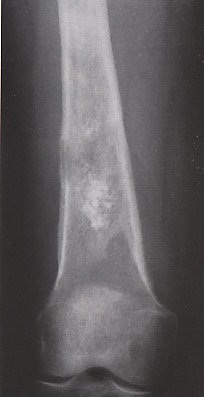

Radiologi:

Didapat 3 macam gambaran radiologi, yaitu:

1.      Gambaran osteolitik, dimana proses destruksi merupakan proses utama.

2.      Gambaran osteoblastik, yang diakibatkan oleh banyak pembentukan tumor tulang.

3.      Gambaran campuran antara proses destruksi dan proses pembentukan tumor tulang.

Gambaran radiologis didapat adanya gambaran osteolitik dan osteoblatik, pada MRI ditemukan garis destruksi.

Pada MRI ditemukan garis akibat proses destruksi dan ekstensi jaringan lunak sel-sel tumor.

Pertumbuhan neoplasma yang cepat mengakibatkan terangkatnya poriosteum dan tulang reaktif terbentuk antara periosteum yang terangkat dengan tulang dan padaX-Ray terlihat sebagai segitiga Codman. Kombinasi antara tulang reaktif dan tulang neoplastik yang dibentuk sepanjang pembuluh darah berjalan radier dari kortek tulang ke arah masa tumor membentuk gambaran Sunbrust.

Radiologi: Tampak sebagai lesi osteolitik ditengah metafisis tulang dengan bercak- bercak kalsifikasi yang berasal dari matriks kartilago disertai proses destruksi kortek, sehingga tumor dapat dilihat meluas ke jaringan lunak disekitarnya.

Gambaran patologis menunjukkan lesi di tengah metafisis dengan bercak kalsifikasi, gambaran patologis terdapat sel ganas di tengah lamellar.